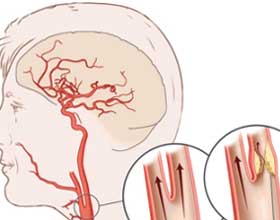

Атеросклероз является довольно распространенным заболеванием. Основным фактором, способствующим его развитию, считается повышенный уровень холестерина в крови. Это вещество представляет собой вязкую субстанцию, которая оседает на стенках сосудов. Атеросклеротические бляшки сужают сосудистые просветы, что часто приводит к нарушению кровообращения в мозге.

Постоянное повышение артериального давления, сопутствующее этому состоянию, вызывает растяжение стенок сосудов, что увеличивает их проницаемость. В результате происходит постепенное сужение просвета и развитие стеноза. Эти процессы могут привести к отмиранию клеток из-за нехватки кислорода.

В случаях тяжелых форм заболевания, которые не поддаются лечению с помощью медикаментов, требуется проведение хирургических вмешательств. Эти операции направлены на удаление атеросклеротических бляшек и тромбов из артерий, что способствует расширению сосудистых просветов с помощью катетеров.